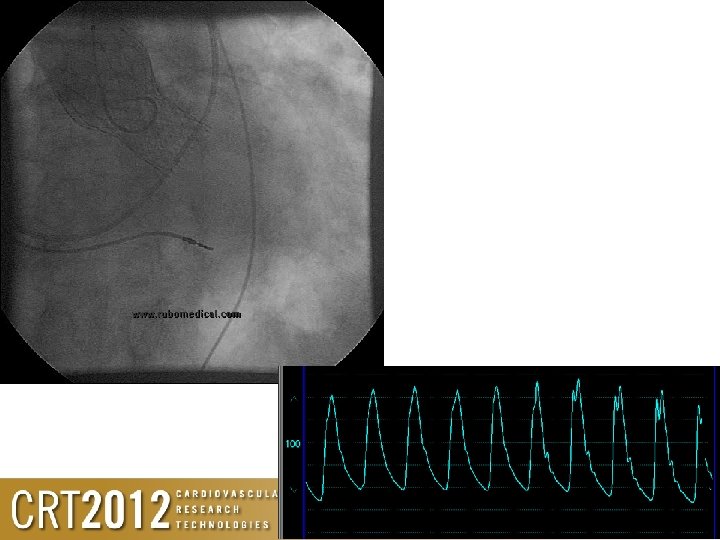

Assessment of paravalvular leak • Echo is great at telling you the obvious • Its poor with the borderline. . . and is confirming what you are already thinking about – If the haemodynamics before the valve is better than after the valve (especially diastolic), then YOU HAVE A LEAK! • Haemodynamics and pressure waveform are best, and when combined with angio gives all you need to know

Poor haemodynamics • Low diastolic pressure • No diacrotic notch • Haemodynamics worsening with time

Angio / haemodynamic guided TAVR • Can be performed reliably, reproducibly and safely • Enables procedure to be performed under local anaesthesia • Shorter recovery time • Less impact on resources • With excellent learnt techniques, you will know – Where the wire is – Where the temporary wire is – Where the valve is and what it is doing